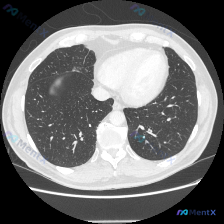

- 影像检查:胸部CT肺窗横断面,右肺中叶近心缘处见局灶性磨玻璃密度影(GGO),边界模糊,内部密度均匀,未见明显实变或支气管充气征;左肺及右肺其余部分正常

- 磨玻璃密度影:边界模糊、密度轻度增高,可见内部血管纹理——符合纯GGO特点

- 位置:右肺中叶近心缘处,孤立性病灶